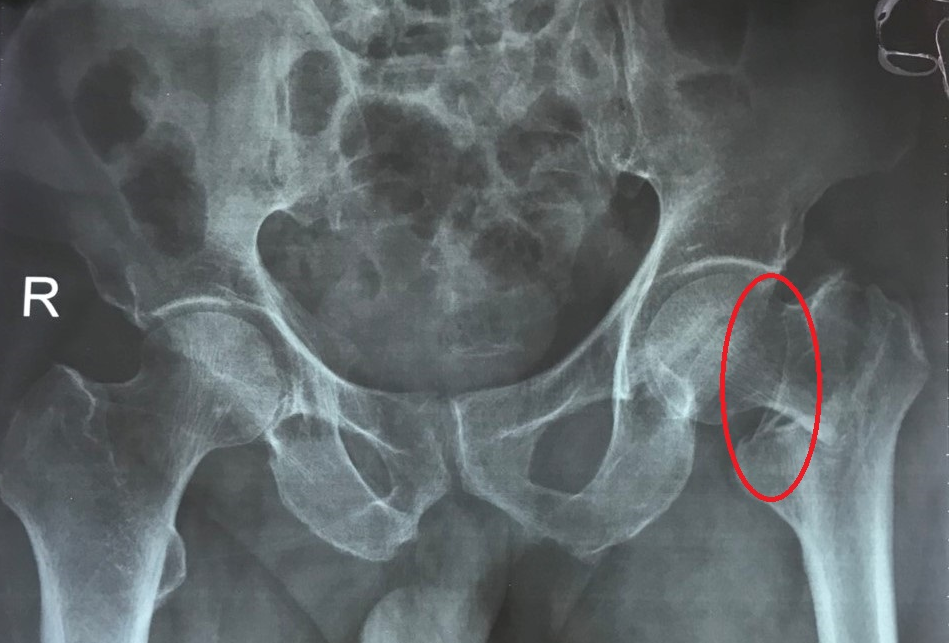

Bệnh nhân B.T.C được người nhà đưa vào Trung tâm Y tế TP. Móng Cái ngày 10/9 trong tình trạng đau khớp háng và chân trái do bị ngã. Sau khi làm các xét nghiệm, chụp X-quang, kết quả chẩn đoán bệnh nhân bị gãy liên mấu chuyển xương đùi trái và được chỉ định mổ thay khớp háng.

Bệnh nhân bị gãy liên mấu chuyển xương đùi trái do ngã